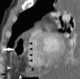

Pericardial hernia

Diaphragmatic hernia is a defect or hole in the diaphragm that allows the abdominal contents to move into the chest cavity. Treatment is usually surgical. [Source: Wikipedia ]